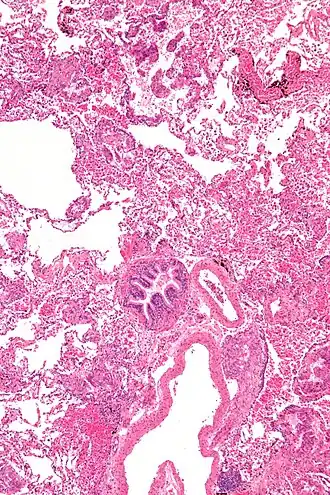

Micrograph of lymphangioleiomyomatosis. H&E stain.

Cette pathologie se caractérise par une prolifération d'un certain type de cellules musculaires lisses qui entraîne la formation de kystes dans les poumons, avec à terme une insuffisance respiratoire. L'évolution de la maladie est toutefois extrêmement variable selon les patientes et de ce fait difficilement prévisible (en particulier il existe des formes peu évolutives de la maladie). Elle peut se faire vers une dégradation de la fonction respiratoire pouvant être invalidante après une dizaine d'années[4].